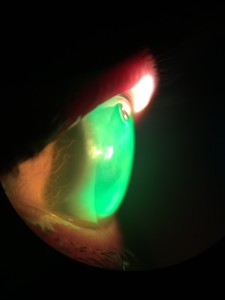

Esta semana quiero comentar este estudio cuyo propósito fué investigar las tasas de éxito y fracaso de la adaptación de la lente escleral en el queratocono grave. Para ello se diseño un estudio de series de casos retrospectivos.

Se propuso la adaptación de lentes esclerales para los 75 ojos incluidos en el estudio. Ocho ojos se sometieron a una cirugía de trasplante debido a la agudeza visual insuficiente con las lentes, intolerancia a los lentes y problemas con el manejo de los lentes. Doce ojos no fueron adaptados debido a la buena agudeza visual en el otro ojo o una contraindicación para el uso de lentes. Tres ojos se adaptaron con éxito con lentes corneales o híbridas. Se prescribieron lentes esclerales en 51 de 75 ojos. La ganancia media en la agudeza visual (lente versus agudeza visual corregida con gafas) fue de 0.54 ± 0.18 (fracción decimal, optotipo Snellen). Siete ojos se perdieron durante el seguimiento, cuatro ojos abandonaron el uso de la lente escleral debido a la incapacidad para manejar las lentes, y cuarenta ojos usaron las lentes en su última visita de seguimiento, con un intervalo de seguimiento promedio de 30.15 ± 12.83 meses.

En conclusión, cuarenta de los 51 ojos con queratocono grave que de otra forma se habrían sometido a cirugía de trasplante se trataron con éxito con el uso de lentes esclerales a largo plazo. De esta manera, la indicación de queratoplastia se redujo a menos de la mitad en esta población de queratocono. Hoy en día, y siempre que no haya una evolución del Queratocono, la lente escleral es una excelente opción de tratamiento.